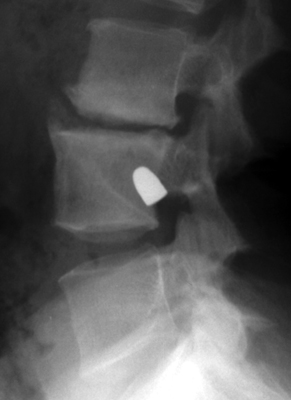

Tumbling Bullet Sign

Post traumatic bone cyst

Two sets of frontal and lateral radiographs, separated only by time, which reveal the "tumbling bullet sign"--which is simply a bullet which changes its location and orientation within a solitary bone cyst. This sign serves two purposes. It is documentation of the evolution of a solitary bone cyst as a corollary of trauma, and reveals the free movement of the foreign body within the confines of the lesion establishing its cystic rather than solid nature. It is similar to the fallen fragment sign.

- Click on the image for a larger versionA - Click on the image for a larger versionB - Click on the image for a larger versionC - Click on the image for a larger versionD

bulletTaxin RN, Feldman R.: The tumbling bullet sign in a post-traumatic bone cyst. Am J Roentgenol Radium Ther Nucl Med 1975 Jan;123(1):140-3.          [See related articles]